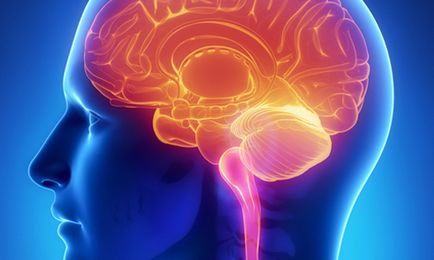

Az evolúció során az emberi agy körül alakult ki egy erős koponya, védi a veszélyeztetett fizikai hatásait a szervezetben. Az agy tovább tart, mint 90% -át a helyet a koponya. Ez három fő részből áll:

Ezután jön a hídban - egy tekercs idegrostok kereszt és a szürkeállomány. Ezen keresztül halad a fő verőér táplálja az agyat. Úgy kezdődik, a fenti nyúltvelő, és bemegy a kisagy.

A kisagy két kis félgömbök csatlakozik „féreg”, és fehérállomány és a szürkeállomány, amely azt. Ez a részleg csatlakozik pár „lábak” hosszú híd, a kisagy és a középagy.

A középagy két talamusz, és két hallás (quadrigeminal szervek). Ezekből halmok kiterjeszteni összekötő idegszálak az agyból a gerinc.

Nagy agy elválasztva egy mély hasíték egy kérges test belsejében, amely összeköti a két agyi részben. Minden agyféltekét egy frontális, temporális, parietalis és az occipitalis. Féltekén kiterjed az agykéreg, amelyben az eredete minden gondolkodási folyamatait.